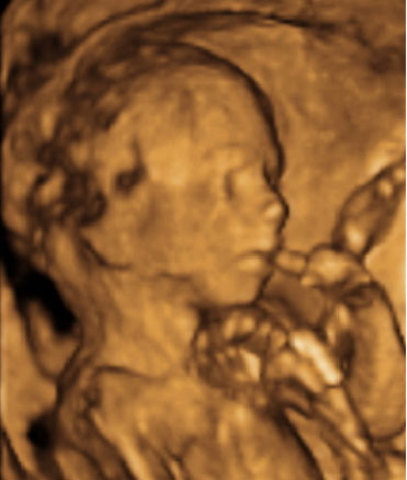

• Semana 28

Semana 28

Los ojos del bebé se comienzan a abrir y cerrar regularmente pero aun cuando el color ya está genéticamente determinado este solo se podrá conocer después de los 6-8 meses de nacido. Su bebé alterna ciclos de sueño/vigilia cada 20 a 30 minutos. Los movimientos fetales se hacen muy obvios cuando usted se relaja, sentada o acostada, especialmente durante la noche. Los rasgos faciales son muy claros

• Semana 29